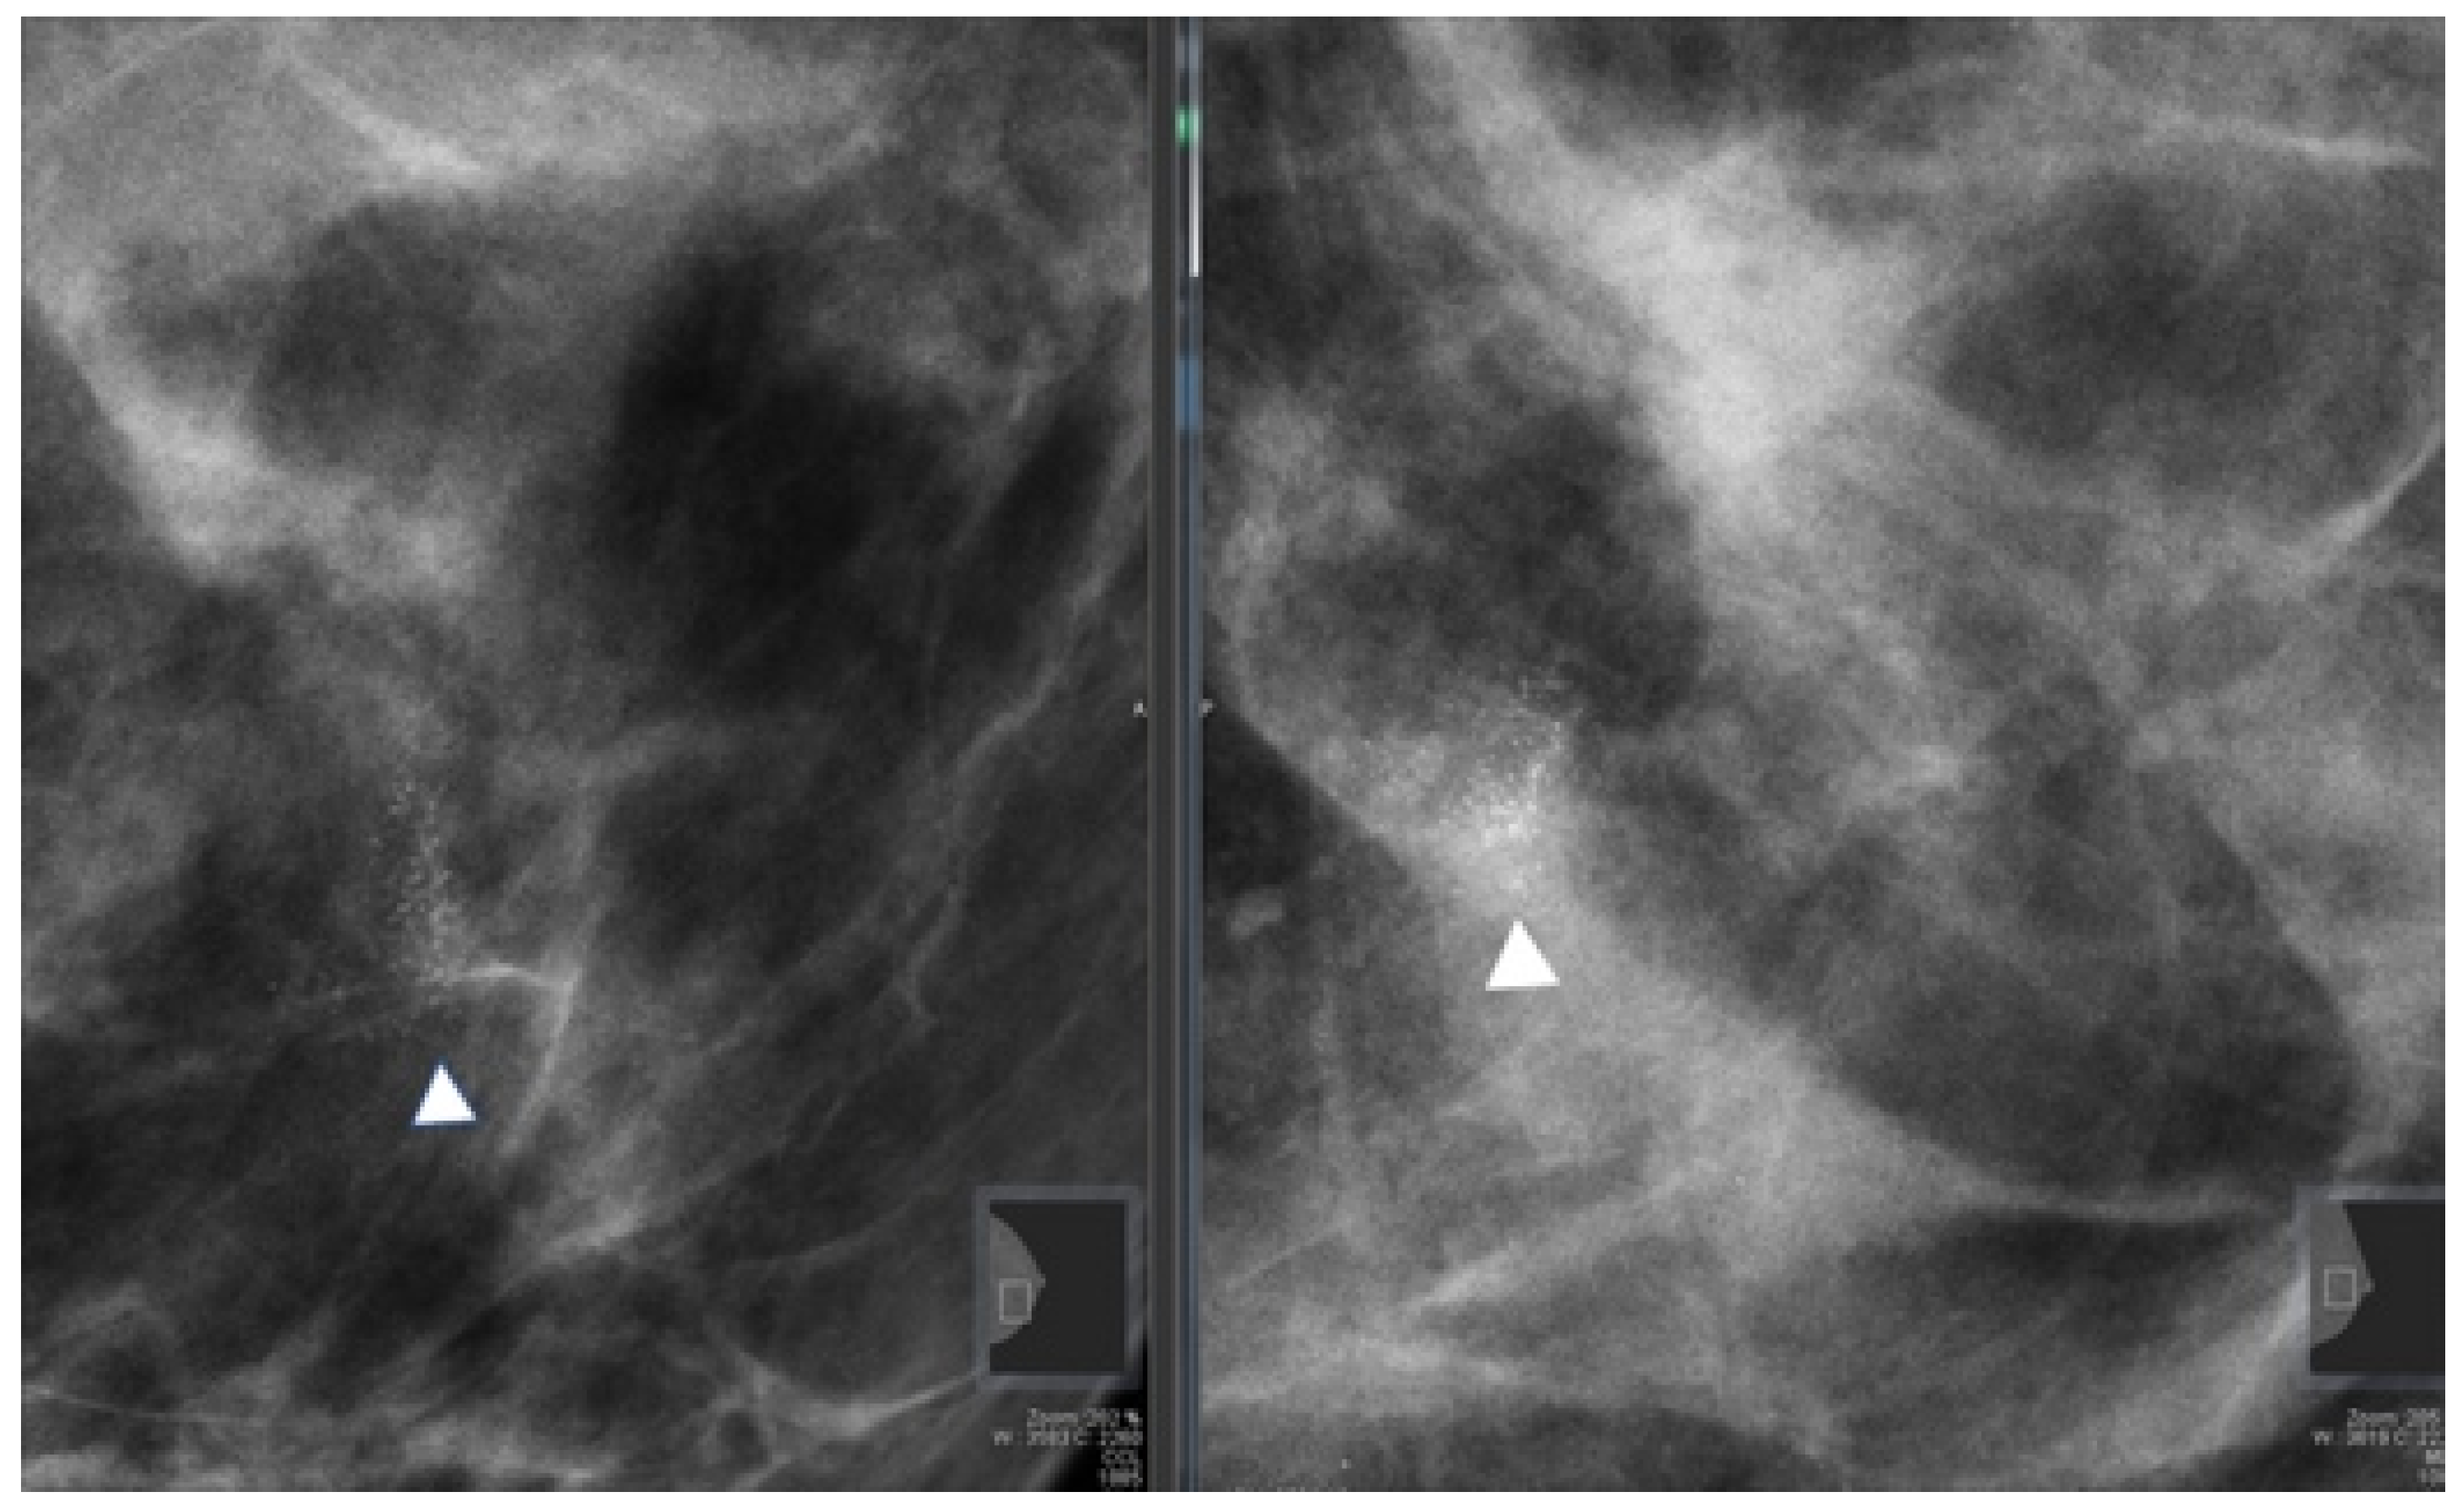

| Microcalcifications | 123 (87.2) |

| Nodule | 17 (12.1) |

| Nodule with microcalcifications | 1 (0.7) |